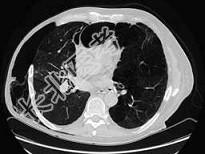

- 单项选择题男,68岁, 胸闷、气短1年余,加重1周, 右胸有手术史,结合CT图像, 最可能的诊断是 ( )

A、右侧气胸并皮下气肿、左侧肺气肿

B、右侧气胸并皮下气肿、左侧肺不张

C、双侧肺气肿

D、右侧气胸并皮下气肿

E、右侧肺间质病变、左侧肺气肿